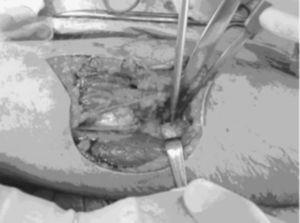

El diagnóstico se efectuó mediante la exploración clÃnica (fig. 1) y se confirmó con una ecografÃa y en cuatro casos con una RMN (fig. 2)

Figura 1. Imagen que muestra el tÃpico «signo del hachazo» de las roturas distales del tendón del bÃceps braquial.